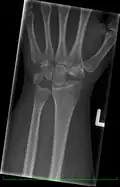

Left hand x-ray with Kienbock's Disease showing 4 mm negative ulnar variance and Kienbock's Disease Stage IIIB -

Left hand x-ray with Kienbock's Disease -